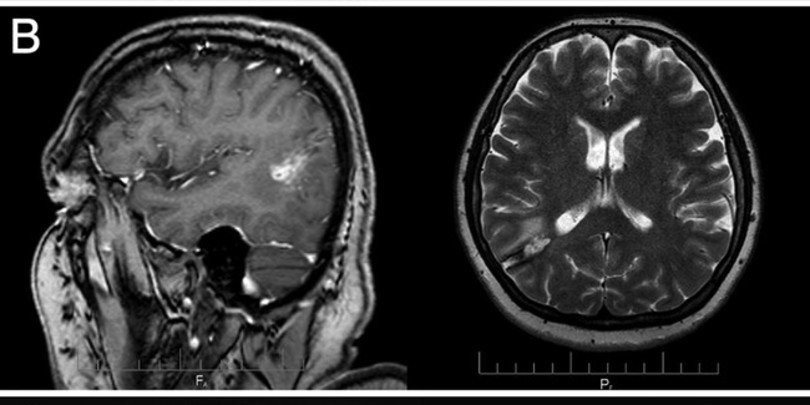

ფოტო: Journal of Neurosurgery

თებერვალში შევიტყვეთ, რომ საქართველოში ქალის ტვინიდან 15-სანტიმეტრიანი ცოცხალი პარაზიტი Taenia solium, ანუ ღორის სოლიტერი, ამოიყვანეს. ქართველმა ქირურგებმა ეს შემთხვევა დეტალურად აღწერეს, მათი ნაშრომი კი ახლახან რეფერირებად გამოცემაში Journal of Neurosurgery გამოქვეყნდა.

ონკოლოგიური ისტორიის მქონე 54 წლის ქალი ქირურგებთან ტვინის სიმსივნის დიაგნოზით მივიდა. ამოკვეთის მცდელობისას ექიმებმა ტვინში 15-სანტიმეტრიანი ცოცხალი ჭია შენიშნეს.

ამოყვანილი ჭია შემდგომში პარაზიტოლოგიის ინსტიტუტმა შეისწავლა. დადასტურდა, რომ ქალს ტვინში მართლაც ზრდასრული თასმისებური ჭია, T. solium, ჰყავდა. ტვინის ქსოვილის მიკროსკოპული კვლევით თასმისებური ჭიის კვერცხებიც შენიშნეს, რომლებიც განვითარების სხვადასხვა სტადიაზე იყო; მათ სპეციფიკური სქელი, ზოლიანი გარსები ჰქონდა.

ოპერაციიდან რამდენიმე თვის განმავლობაში ქირურგები შემთხვევის შესწავლასა და აღწერაზე მუშაობდნენ. ნაშრომმა რეცენზირება გაიარა და რეფერირებად სამეცნიერო ჟურნალში გამოქვეყნდა. გამოდის, სამეცნიერო ლიტერატურაში ეს პირველი დადასტურებული შემთხვევაა, როცა ადამიანის თავის ტვინში ზრდასრული ღორის სოლიტერი დაფიქსირდა.